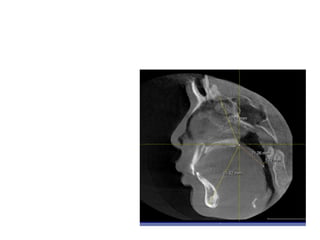

RME

• Maxillary constriction in particular has been

postulated to play a role in the pathophysiology

of OSA because of its association with low tongue

posture that may contribute to the orophayrnx

airway narrowing (Subtelny 1954).

• Pirelli et al. grouped 31 children with OSA and

followed them up to 4 months after RME

treatment. All of these children had their apnea-

hypoapnea index decreased while their mean

maxillary cross sectional width expanded to

about 4.5mm.